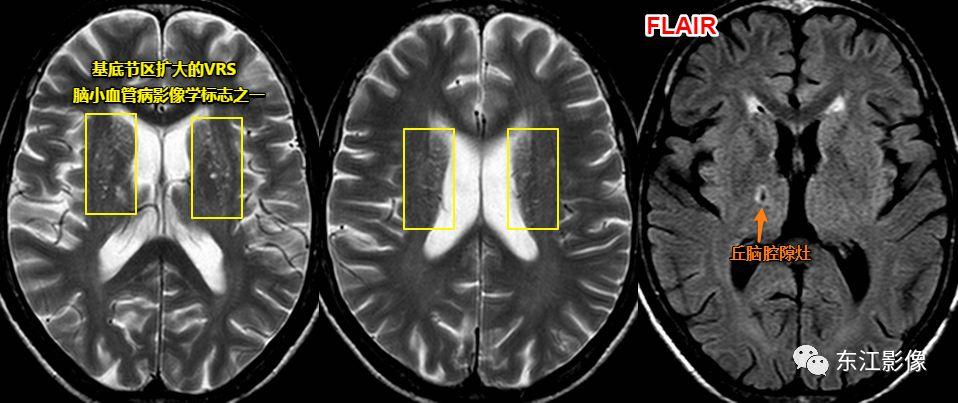

注意,扩大的血管周围间隙也是脑小血管病的影像学标志之一,但并非所有扩大的血管周围间隙均与脑小血管病有联系。

一般认为,基底节区中上区域扩大的血管周围间隙多与脑小血管病有关系。

基底节区扩大的血管周围间隙,丘脑腔隙灶典型影像,均为脑小血管病影像学标志。